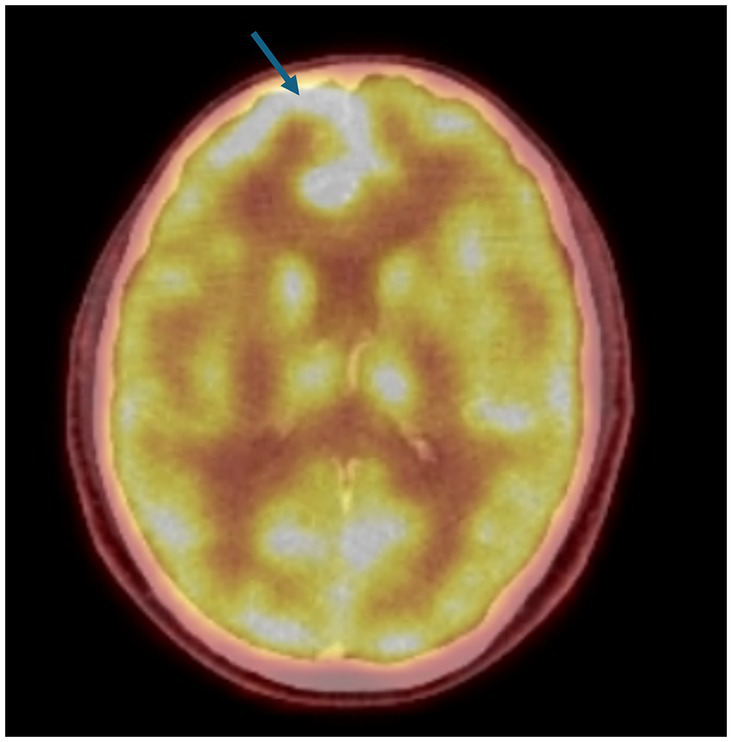

Based on this result, nivolumab was administered, almost 2 years after initial diagnosis (23 May 2019), with ipilimumab being added in the fourth cycle. The PET-CT scan, 3 months later, revealed a significant partial response (Figure 1).

Figure 1

On 23 May 2019, the patient was started on 240 mg of nivolumab every 14 days. As the patient tolerated the treatment well, from the fourth cycle onwards, a 1 mg/kg dose of ipilimumab was added every 21 days. A significant partial response was observed in the PET-CT scan performed on 19 August 2019, after 6 cycles of nivolumab and 2 cycles of ipilimumab.